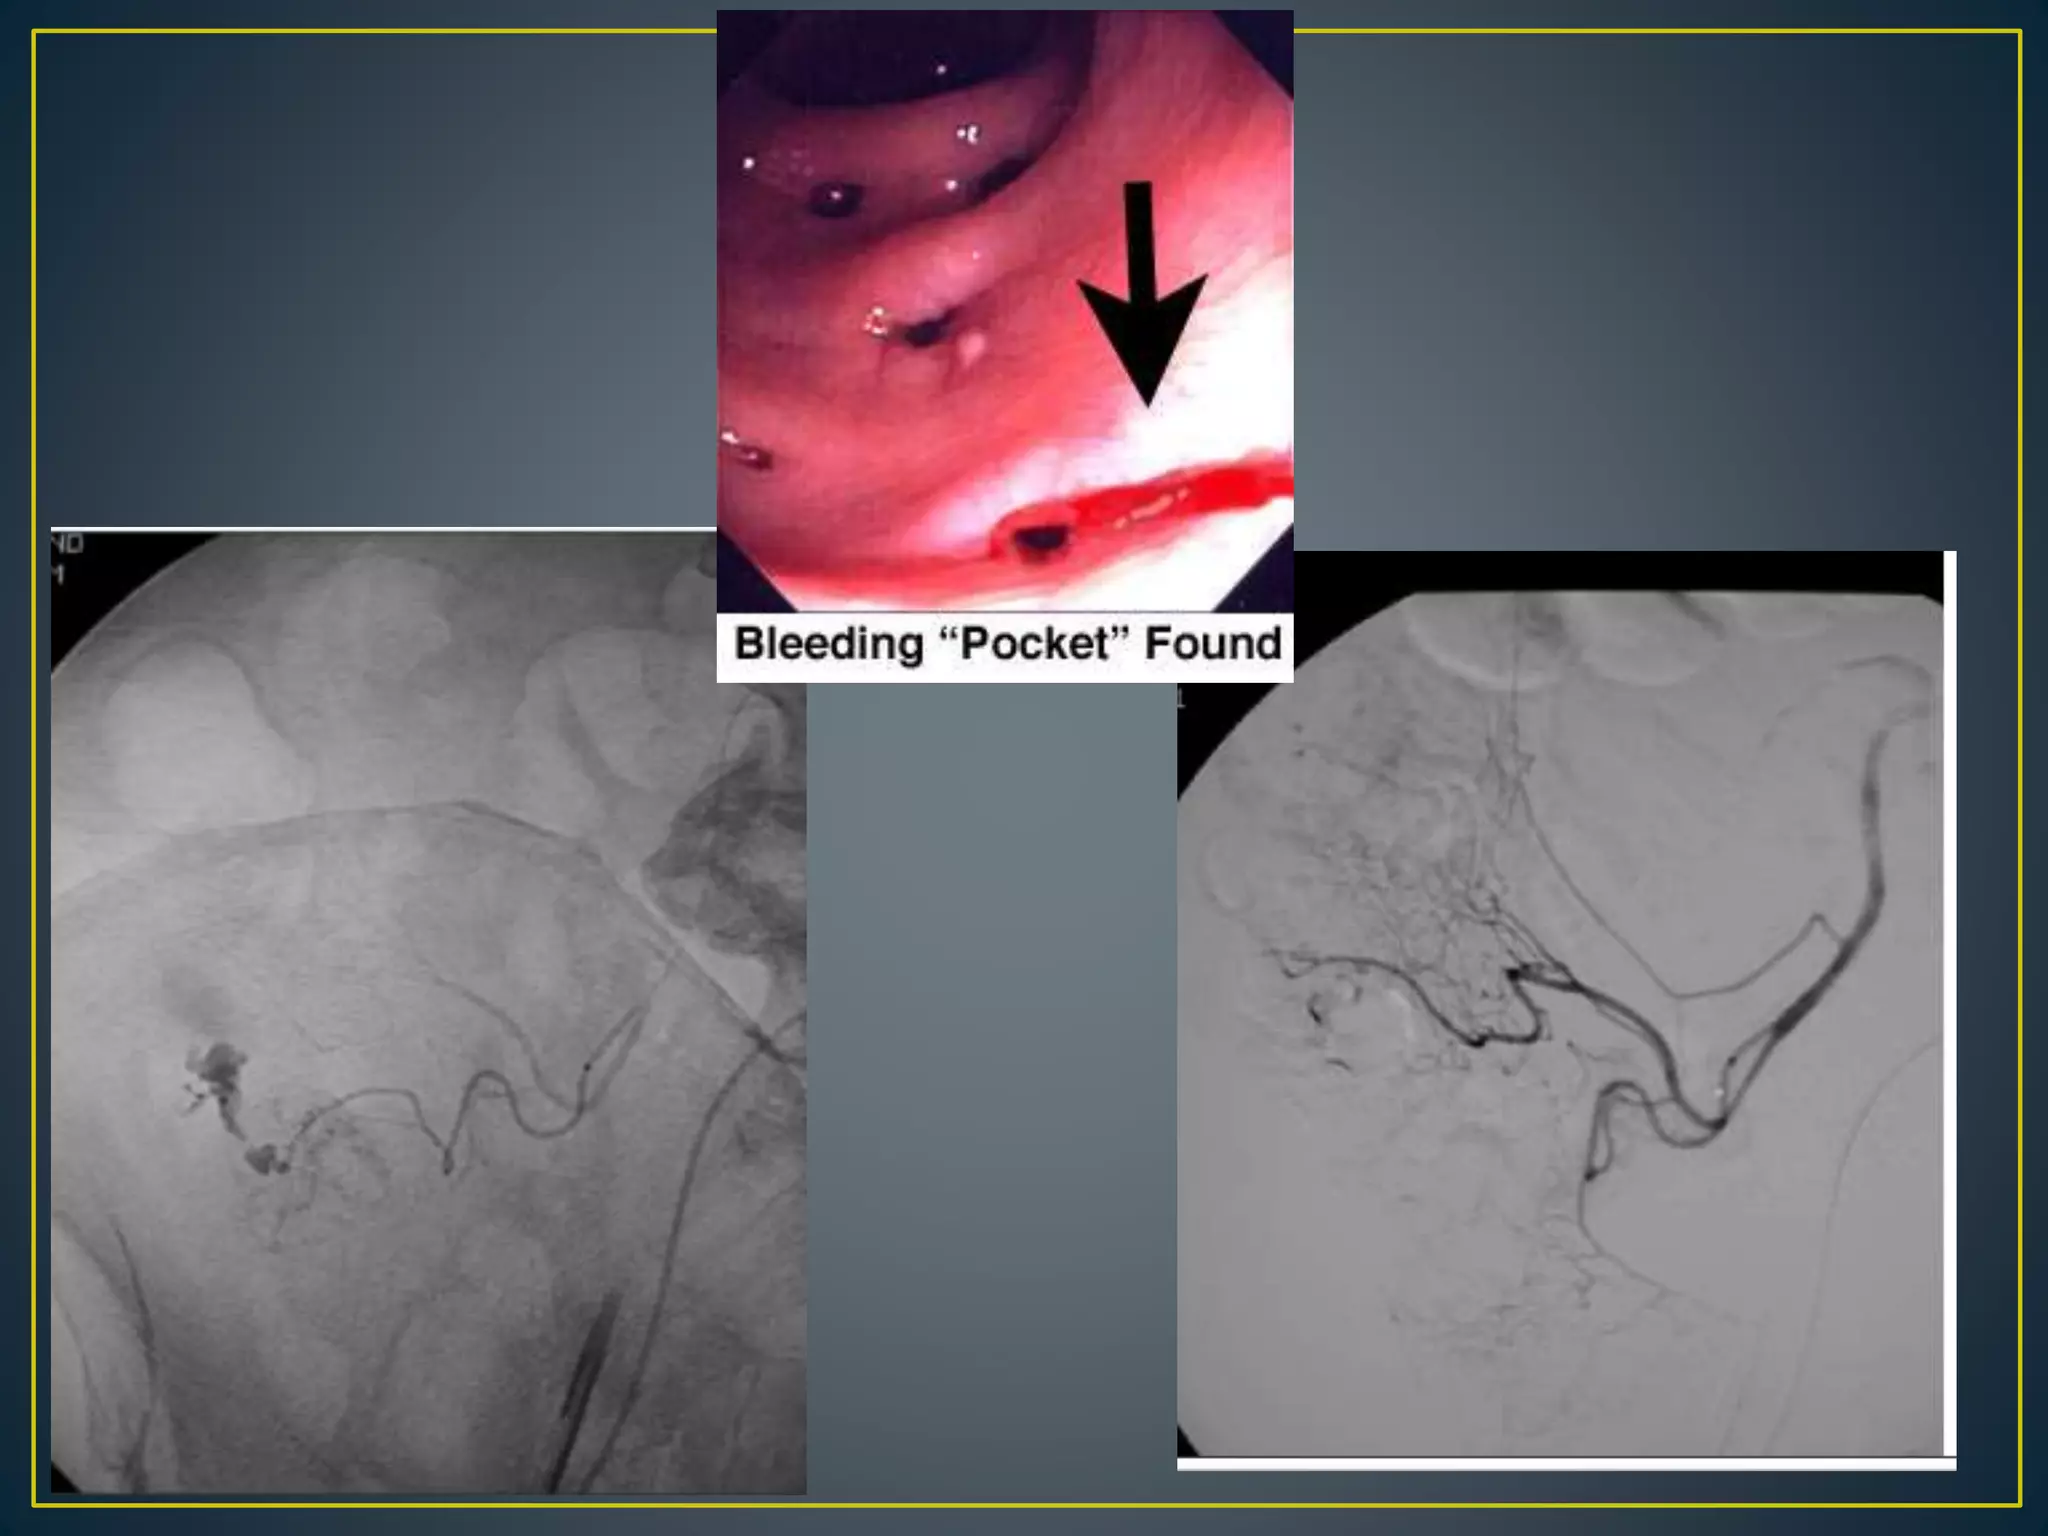

• Arteriovenous malformations located in the cecum and

ascending colonLesion affecting elderly persons older

than 60 years

• Composed of clusters of dilated vessels, mostly veins, in

the colonic mucosa and submucosa

• Colonic angiodysplasias are believed to occur as a result

of chronic, intermittent, low-grade obstruction of

submucosal veins as they penetrate the muscular layer

of the colon

• Angiodysplasia tends to cause slow but repeated

episodes of bleeding

• Angiodysplasias can be easily recognized by

colonoscopy as 1.5- to 2-mm red patches in the mucosa

• Angiodysplasia is diagnosed by early and then

persistent filling of a draining vein and by an abnormal

cluster of vessels in the bowel wall

• Lesions can be multiple. The abnormality is identified by

early venous drainage from one portion of the bowel or

a "tram track" sign from simultaneous opacification of the

feeding artery and draining vein.

• Contrast extravasation usually is not seen. Because

angiodysplasia is relatively common in elderly patients

and may be an incidental finding, other sources of

bleeding should be considered.